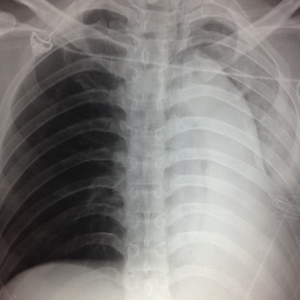

如何拍胸片照片

拍胸片的照片看一下

拍个胸片

拍胸片照片

胸片图片

拍胸片